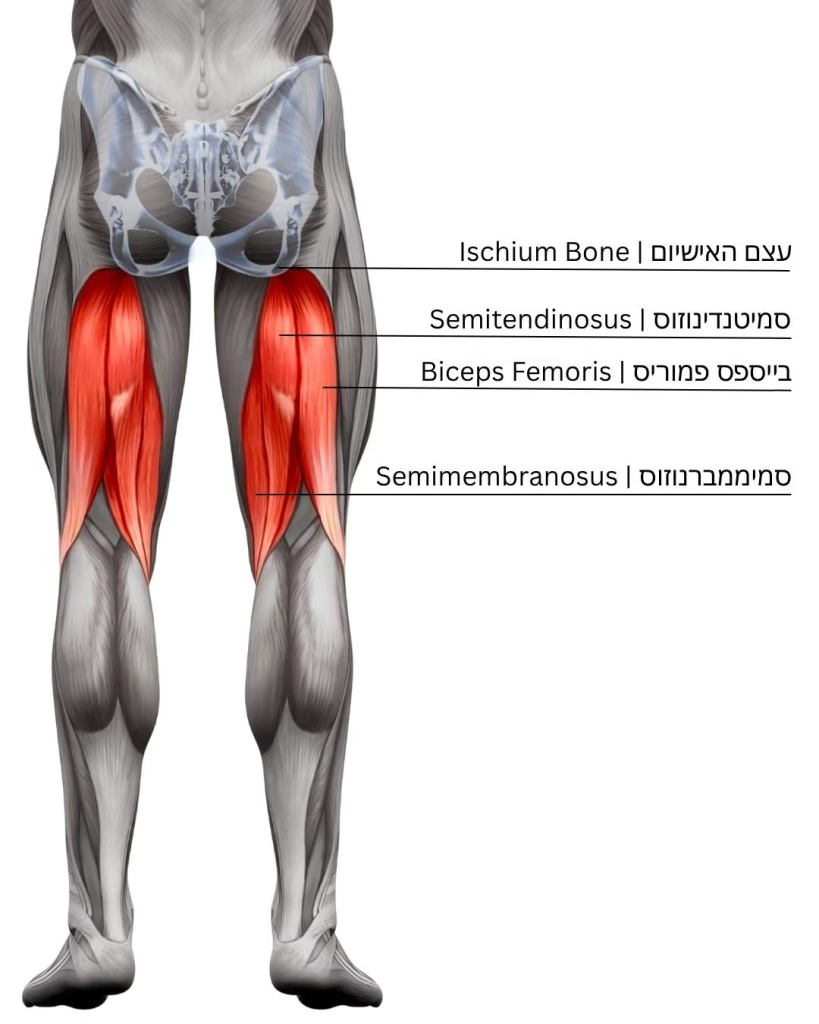

תסמונת הרצועה האיליוטיביאלית

Iliotibial band syndrome

פציעה שמתייצגת עם כאב צידי בברך שיופיע לרוב במהלך הריצה ואף יחייב הפסקה של הריצה. הכאב יכול להחמיר בריצה בירידות. ללא טיפול, הכאב צפוי להופיע יותר ויותר מוקדם במהלך הריצה, להחמיר בעצימותו ואף עלול להימשך לאחר הפסקת הריצה לאורך זמן.

המבנה האנטומי המעורב בפציעה זו הוא רצועה ארוכה המחברת בין עצם האגן לעצם השוק ועוברת בחלק הצידי של הברך – ה-Iliotibial Band. בעבר היה מקובל לחשוב שהסיבה לכאב היא חיכוך במהלך התנועה המחזורית של הרצועה על עצם הירך המרוחקת בזמן פעילות. מחקרים עדכניים שללו את תאוריית התנועה המחזורית והחיכוך והציעו תאוריה חלופית. בזוויות כיפוף של מעל 30 מעלות בברך, הרצועה מפעילה לחץ (Compression) על עצם הירך המרוחקת ועל רקמת שומן הנמצאת ביניהן. רקמת השומן היא רקמה רגישה עם מבנים עצביים והפגיעה בה מעוררת את הכאבים.

במסגרת תהליך האבחון חשוב לשלול סיבות אחרות לכאבים בצד הברך, הכוללות: פגיעה במניסקוס צידי בברך, תגובת מאמץ מקומית של העצם ועוד. על כן, חשוב לעבור הערכה רפואית מקצועית של מומחה בתחום.

הטיפולים המקובלים לפציעה זו היא הפסקה זמנית של הפעילות מעוררת הכאב ופיזיותרפיה מותאמת. בעקבות הגילויים החדשים על הסיבות לכאב בתסמונת זו, קיימת מחלוקת גדולה על התרגילים המומלצים כטיפול. עם זאת, עדיין מקובל להיצמד לעקרונות הבאים:

- תרגול עם גליל קצף - Foam Rolling.

- ביצוע מתיחות של הרצועה ועבודה על הגמישות שלה.

- חיזוק שרירים סביב האגן והירכיים.

- שימוש ב-Taping.

- העמסה הדרגתית וחזרה מדורגת לריצה.

מחקרים עתידיים יתמקדו בבחינה של שינוי טכניקת ריצה כטיפול מועדף (רוחב צעד גדול יותר, Cadence גבוה יותר ועוד).

במקרים עקשניים ניתן יהיה לשקול טיפול בנוגדי דלקת בכדורים וכן טיפול בהזרקות. הזרקה בודדת של חומרים סטרואידים היא עדיין טיפול מקובל, אולם הזרקות סטרואידים חוזרות אינן מומלצות. ניתן גם לשקול הזרקות של חומרים ביולוגים (כדוגמת פלסמה עשירת טסיות).

טיפולים ניתוחיים נדירים בתסמונת זו וכוללים שחרור מקומי, הארכה של הרצועה או הוצאה חלקית של הרצועה ורקמות פגועות.